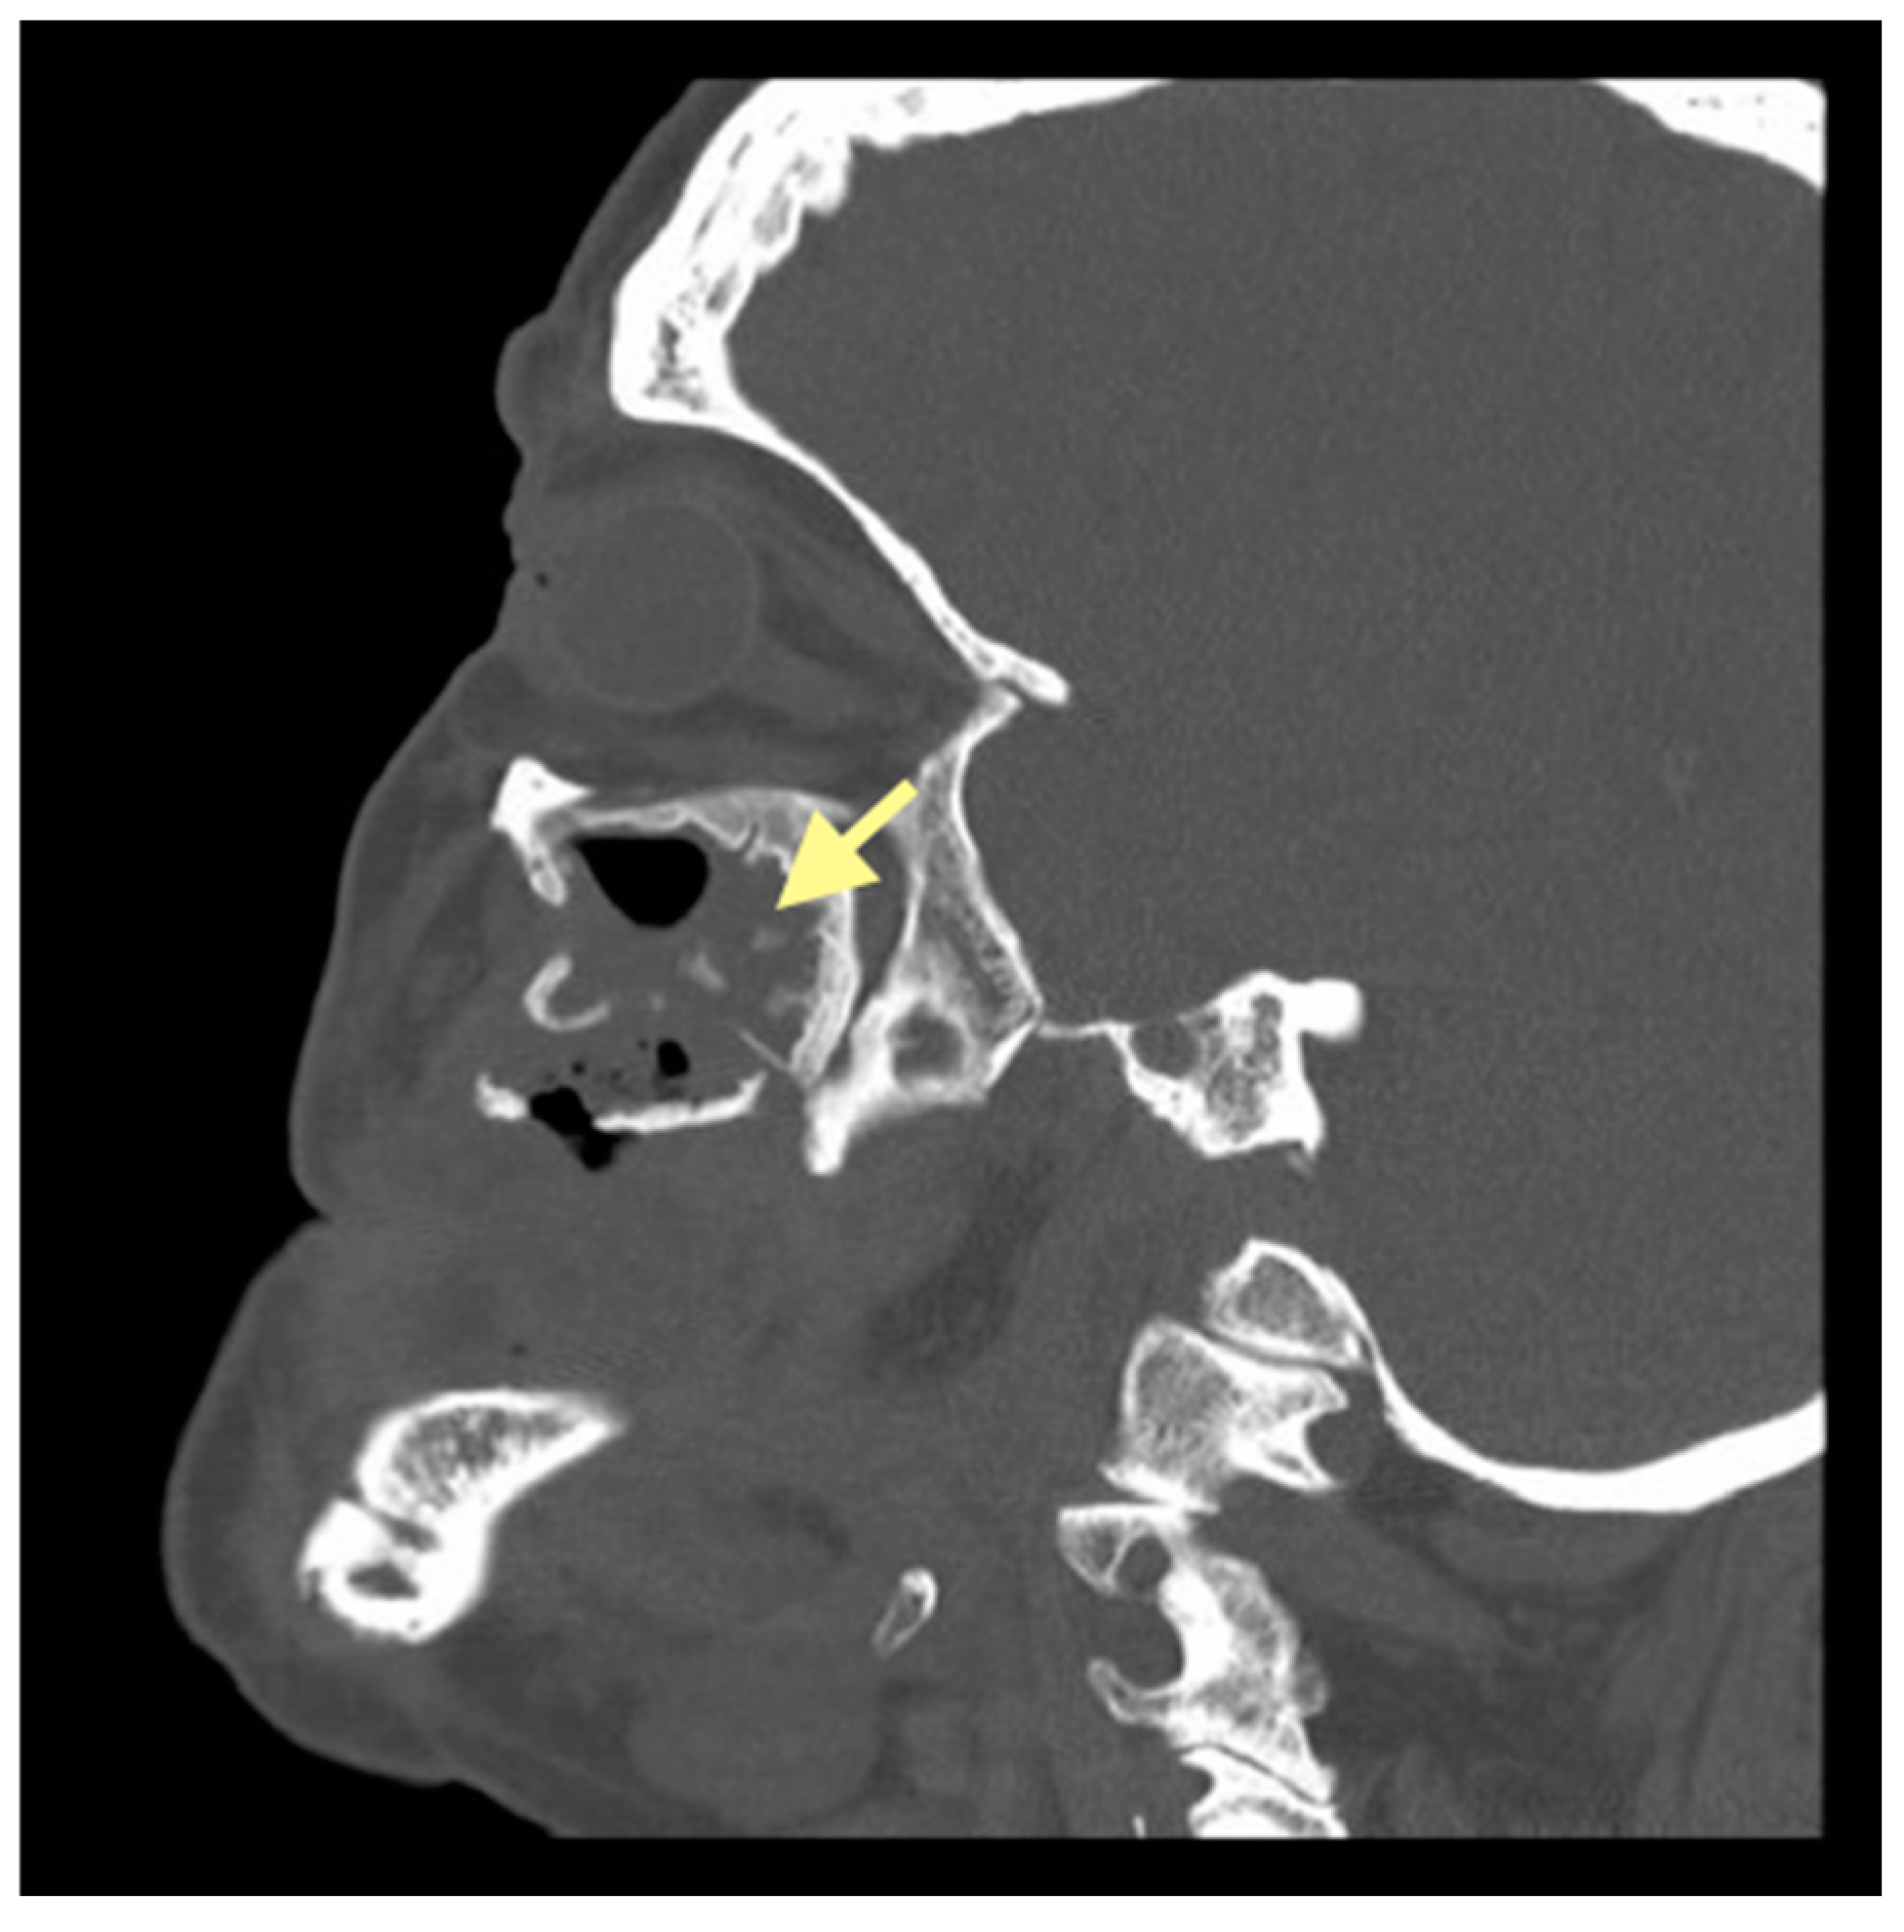

Figure 9.

CT of the head and facial bones (16 December 2024).

The third patient was a 75-year-old female with osteonecrosis of the mandible and maxilla in the fourth and in the second quadrant (see Figure 7, Figure 8 and Figure 9). The patient had third-stage jaw osteonecrosis. In 2023, the patient was diagnosed with osteonecrosis of the upper and lower jaw caused by antiresorptive therapy (until August 2021, the patient regularly used Zolendronic acid; then, this drug was replaced by the RANKL inhibitor Denosumab). The treatment was periodically complicated by submandibular and submental abscesses. In addition, due to the progression of the underlying disease, constant courses in chemotherapy were administered. The patient underwent three operations, which included sequestrectomy of the jaw with simultaneous use of A-PRF, antrotomy with revision of the maxillary sinus, closure of the oroantral communication, and opening and revision of abscesses of the soft tissues (see Figure 10 and Figure 11)